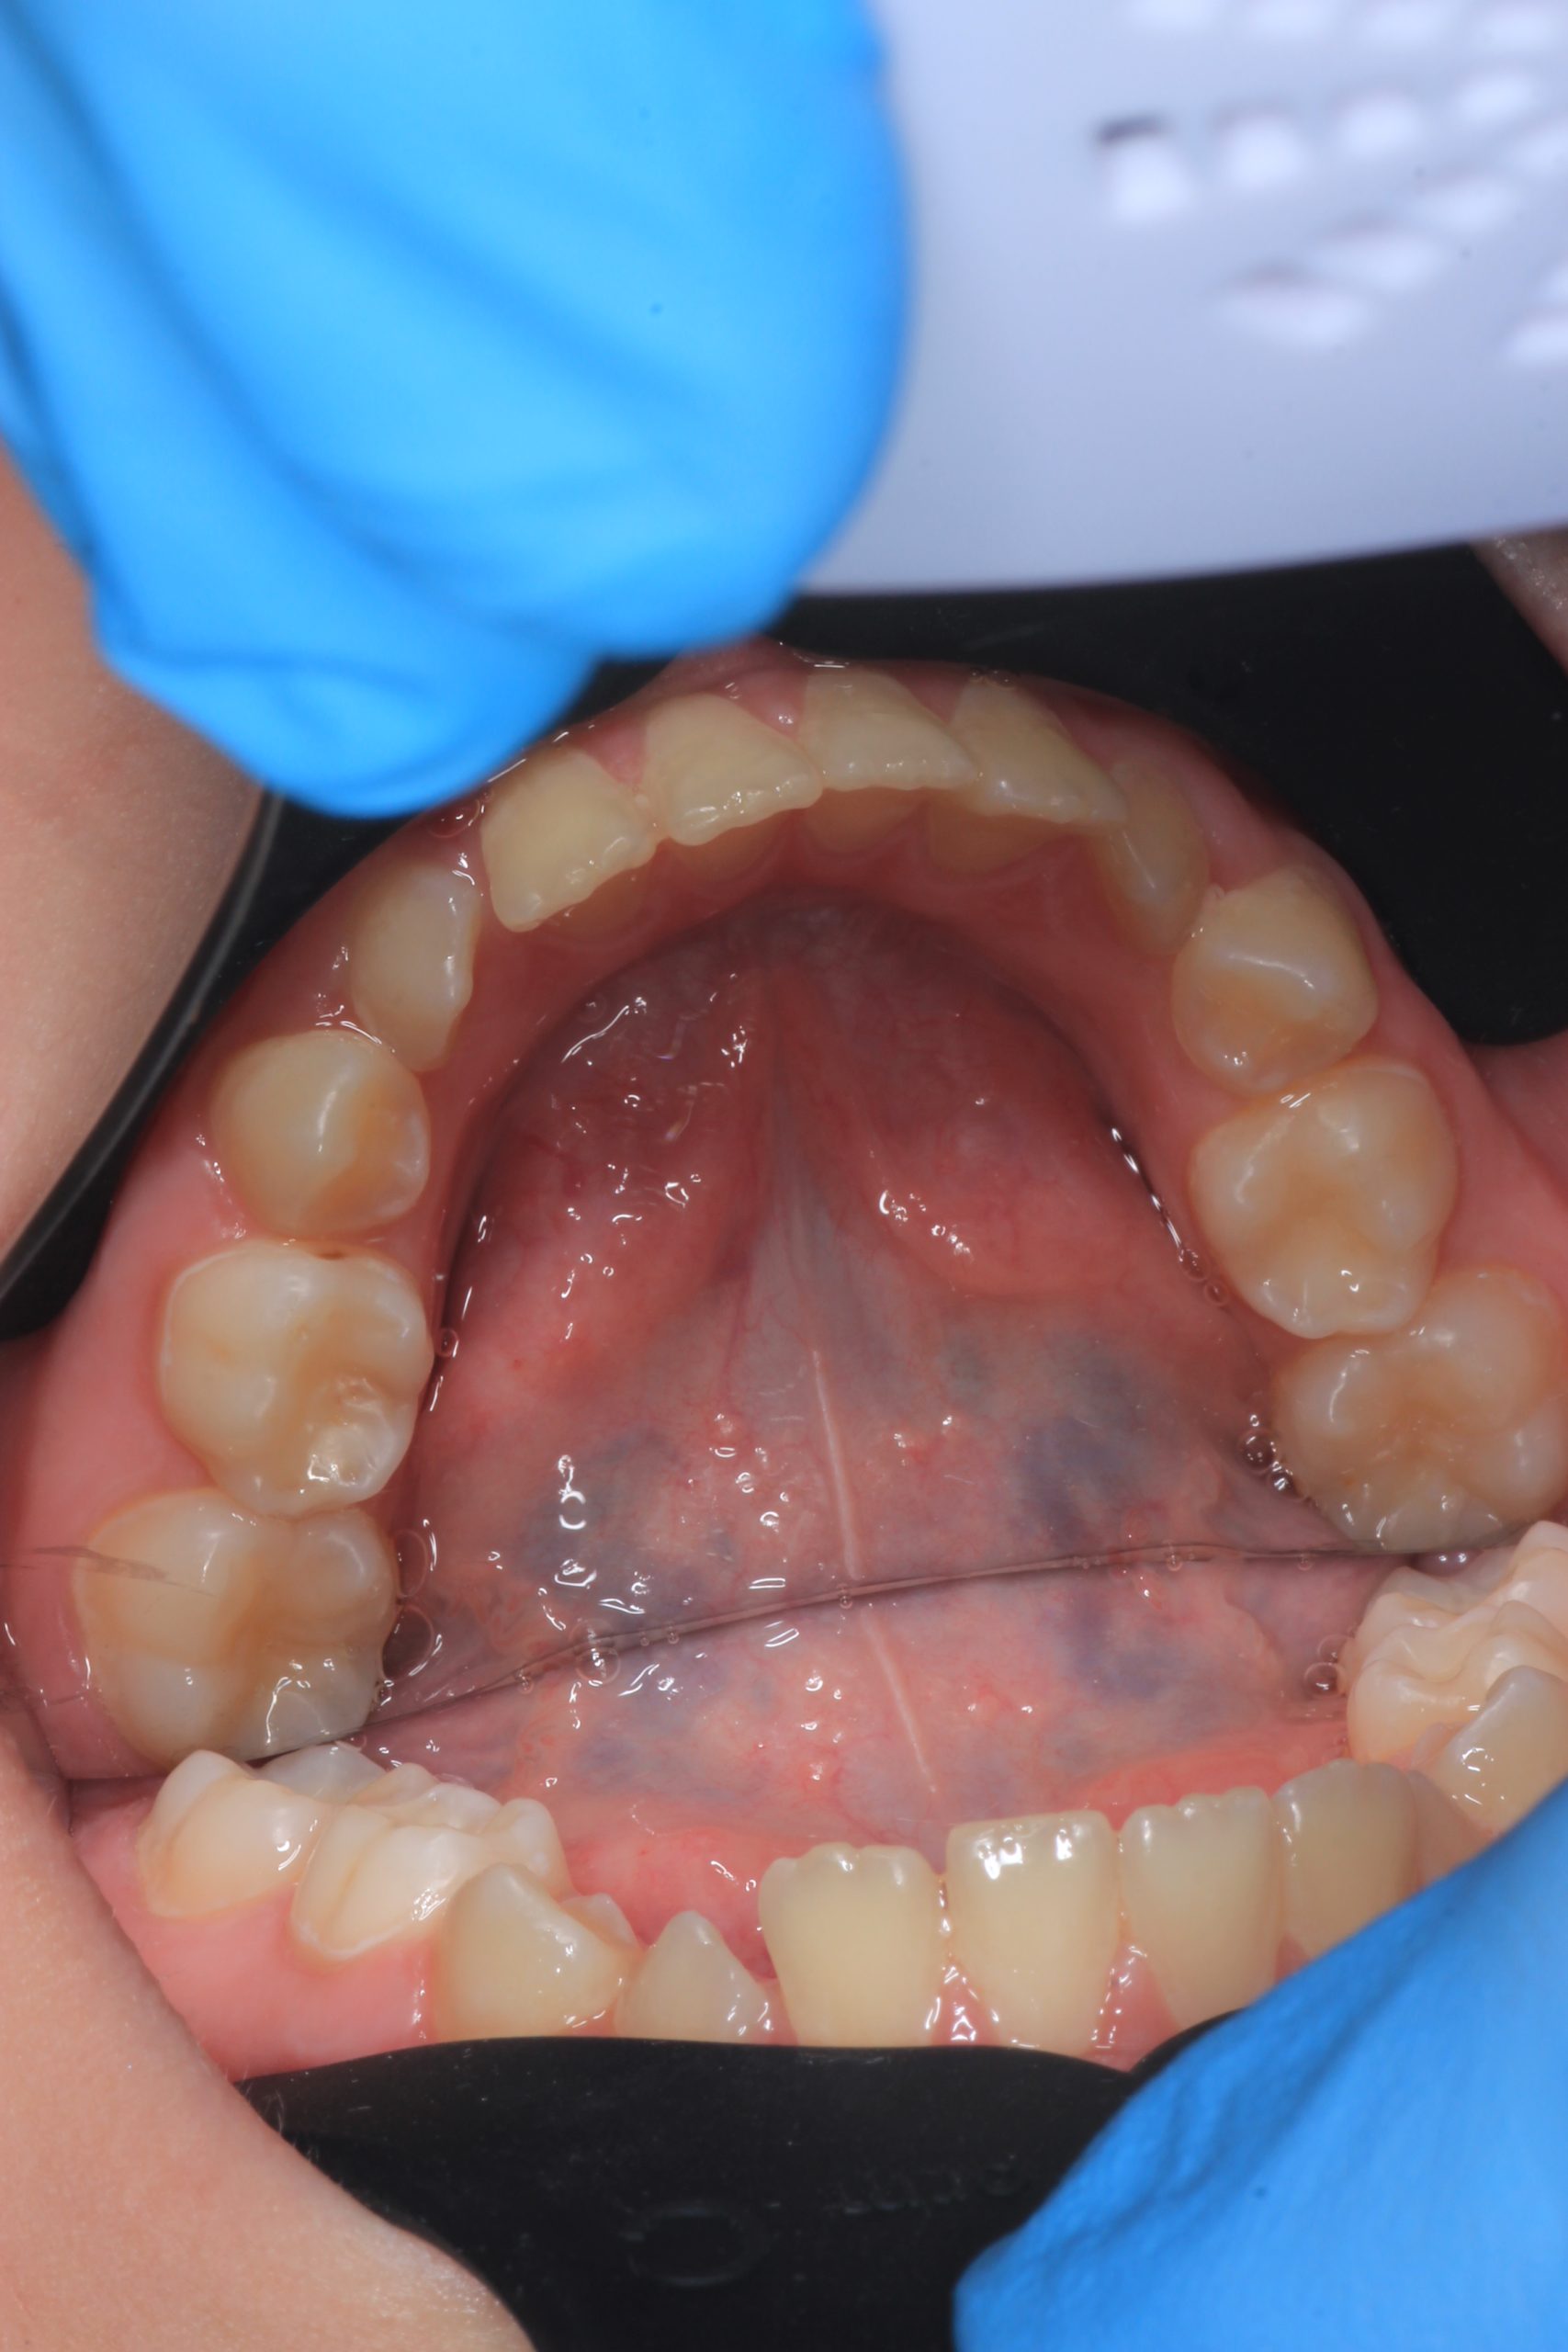

- Detailed Examination

We examine the condition of teeth, gums, and bite. - Plaque Disclosure with Special Indicators